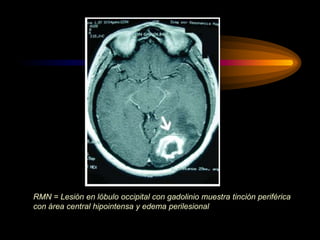

• En la TAC y RM con contraste se

delimitadas por un halo hipercaptante

RMN = Lesión en lóbulo occipital con gadolinio muestra tinción periférica

con área central hipointensa y edema perilesional

Diagnóstico • En laTAC y RM con contraste se visualizan como lesiones hipodensas delimitadas por un halo hipercaptante (captación en anillo) y edema perilesional T A C Permite obtener cortes transversales desde diversos ángulos. Permite distinguir, con gran resolución, las alteraciones y localización de los tumores. En general es necesario administrar un producto de contraste para mejorar la Es la prueba diagnóstica de primera elección, pues es la que permite las imágenes más precisas R M N

RMN = Lesiónen lóbulo occipital con gadolinio muestra tinción periférica con área central hipointensa y edema perilesional